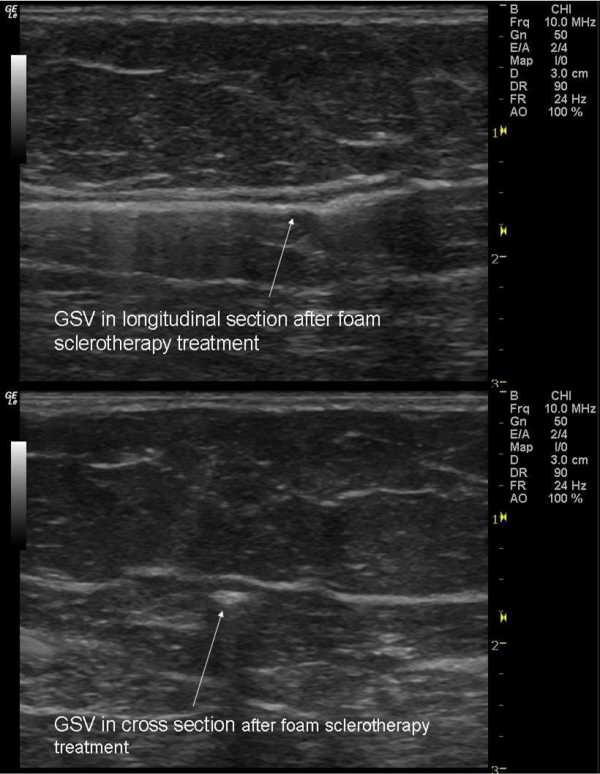

Принцип склеротерапии такой же, как и лазерной, только в вена «склеивается» специальным клеем-склерозантом. Бывает еще пенная склеротерапия, когда склерозант прямо перед манипуляцией взбивается в пену. Так он лучше заполняет просвет сосуда. Однако для пенной склеротерапии существуют противопоказания. Особенно опасно такое вмешательство при наличии патологии сердца, порока, который связан с «овальным окном» — есть опасность попадания пены по венозной системе в сердце.

Склерозирование

Лечение патологии варикоза заключается во введении лекарства жидкой формы. При помощи микроукола вводится специальное вещество, разрушающее стенки вен изнутри. После процедуры на месте укола можно обнаружить воспаление, которое в дальнейшем зарубцовывается, а пораженный сосуд склеивается. Сегодня в большинстве клиник применяют пенообразное вещество. После введения в кровеносный сосуд пена расширяется, заполняя сосуд в диаметре. Пациент во время процедуры должен принять горизонтальное положение.

Склерозирование не занимает более 30 минут. Хирургическое лечение не требует нахождения в стационаре. После окончания процедуры на ноги надевают компрессионные чулки. Для восстановления циркуляции крови по глубоким кровеносным сосудам и в целях профилактики тромбоза врач рекомендует пациенту прогуляться в течение 30-ти минут. В течение месяца рекомендуется ношение компрессионного белья, которое разрешается снимать с нижних конечностей только на ночь. Виды лечебного трикотажа в зависимости от степени компрессии определяет лечащий врач.